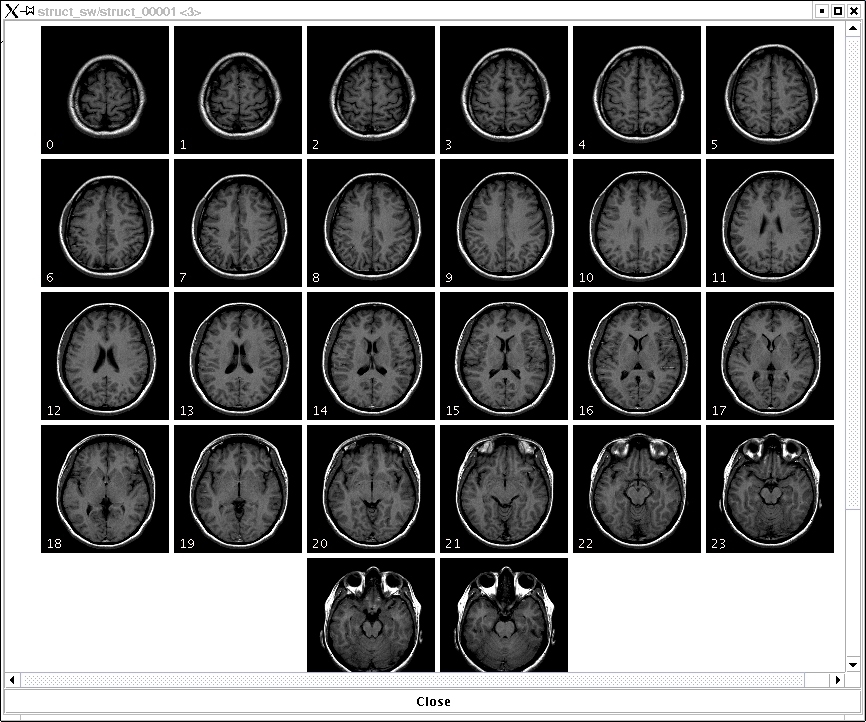

part of Player Photograph

Quite possibly my most revealing photo.